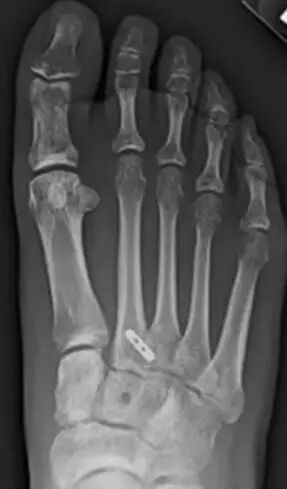

术后影像

可调节带袢钛板

规格:12×4×1.5mm

带线锚钉IV型

规格:2.9×15.5 mm